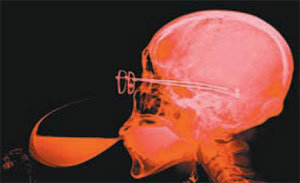

X선으로 자화상과 가족사진을 찍는 X선 아트(사진), 10억분의 1m를 추구하는 나노예술, 사이보그의 탄생을 주제로 한 작품…. 예술가들이 기계공학과 광학, 천문학, 생물학 등 최첨단 과학자와 만나 탄생한 새로운 예술의 세계로 들어가 보자.(station.donga.com)